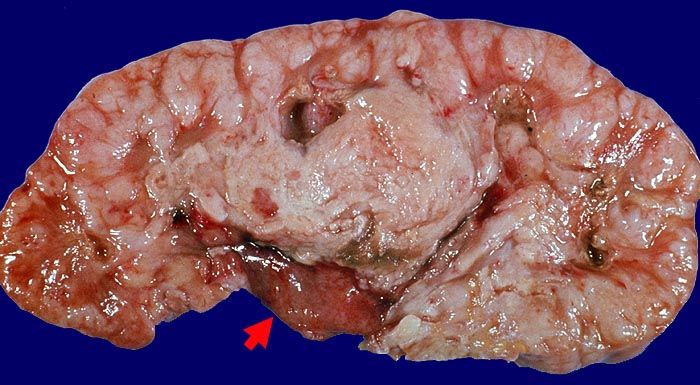

Pathomorphologisch unterscheiden sich Urothelkarzinome bei Phenacetinabusus nicht von sporadischen Urothelkarzinomen abgesehen von ihrer bevorzugten Lokalisation im Nierenbecken und der allenfalls ausserhalb des Tumors in der Harnwegsschleimhaut nachweisbaren Kapillarosklerose.

Morphologische Merkmale:

• Solider Tumor mit fokalen Entzündungsinfiltraten.

• Ureter mit verdickten Kapillaren (Kapillarosklerose).